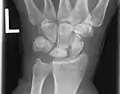

Left hand x-ray with Kienbock's Disease

Left hand x-ray post proximal row carpectomy